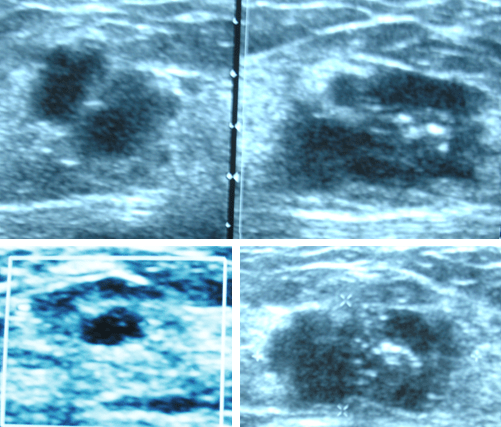

USG of the breast tumours done in Sydney, Australia 2010.